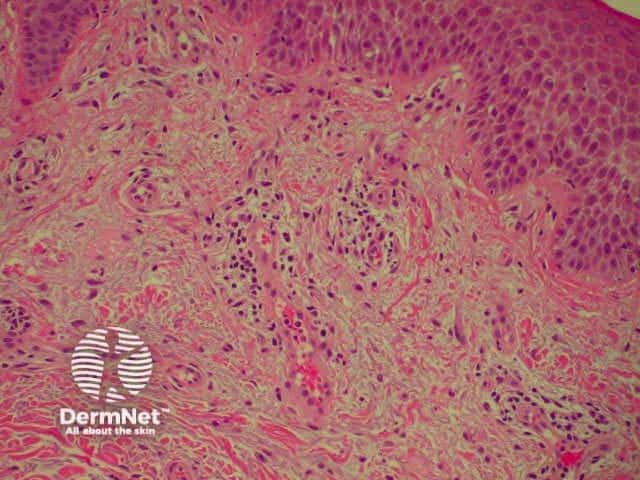

Lichen planus is the idiopathic version of a group of lichenoid disorders characterised by scaling papules or plaques. Link to a clinical description of lichen planus.

The histological features of lichen planus are:

The majority of lymphocytes in the often dense infiltrate are memory cells, identified using histochemistry by positive CD8 and CD45 RO markers.

Direct immunofluorescence nearly always reveals fibrinogen within the colloid bodies. Occasionally IgM and complement are also detected. The immunofluorescence pattern is not diagnostic as the same reactants can also be seen in systemic lupus erythematosus and erythema multiforme.

Lichen planus Lichen planus Lichen planus Lichen planus Lichen planus Lichenoid inflammation